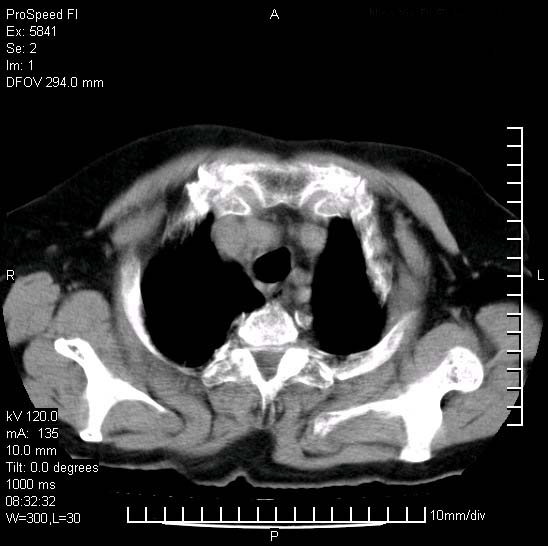

胸痛,咳嗽,气短一周,无发热。右上肺见一结节灶,边缘刺角,内见多个小钙化结节。考虑结核球?肿瘤? 余无异常没有上传。